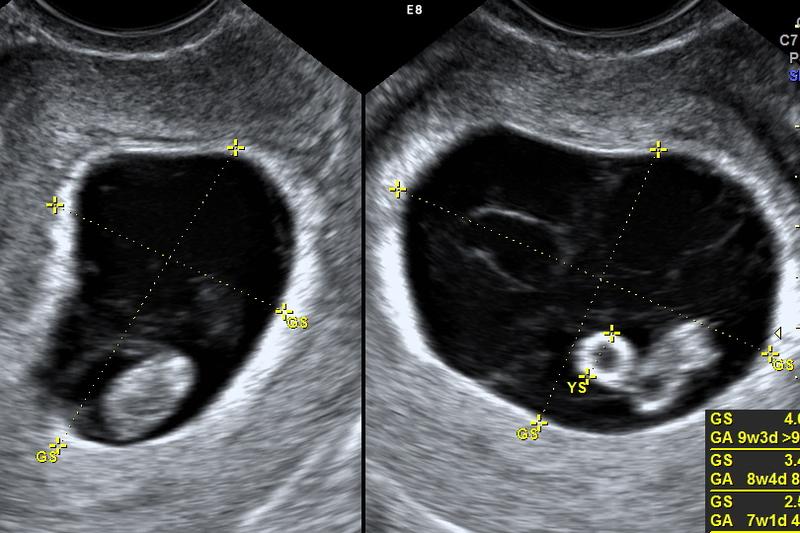

| USG | Możliwość usłyszenia bicia serca maluszka |

Na koniec należy podkreślić, że każda ciąża to niepowtarzalna historia. Przyszłe mamy muszą pamiętać, że nie wszystkie wymienione objawy muszą wystąpić. Niektóre kobiety przechodzą ten czas bez większych zawirowań, podczas gdy inne czują się jak prawdziwe mamy od momentu spełnienia marzeń o macierzyństwie. Ważne jest, aby dbać o siebie, słuchać swojego ciała i pamiętać o regularnych wizytach u lekarza, tak aby z niecierpliwością oczekiwać na pierwsze USG i podziwiać bijące serce swojego maluszka!